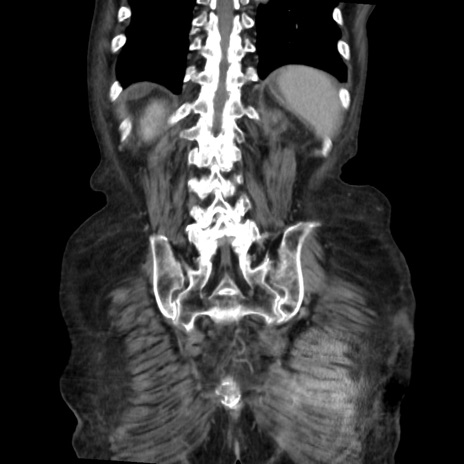

症例31(冠状断像)

【症例】80歳代 女性

【主訴】腹部膨満感

【現病歴】他院にて肝硬変にてフォロー中。1週間前から便秘、腹部膨満感、臍部腫瘤あり受診となる。

【既往歴】肝硬変

【身体所見】腹部膨隆あり、皮膚変化なし、疼痛なし。

【データ】WBC 4600、CRP 0.25